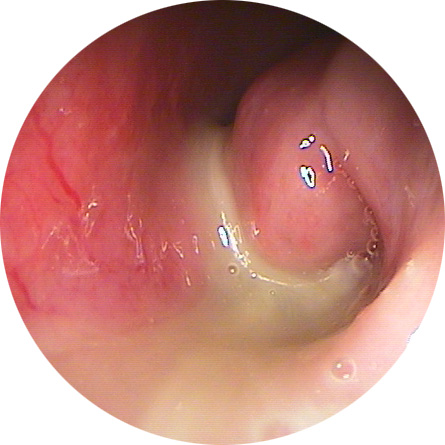

- 신체검사 : 코 내부를 확인하기 위해 비경(Context: endoscope) 또는 비인두 내시경을 사용합니다.

약물 치료에 반응이 없는 경우에는 내시경을 통한 부비동 수술을 고려할 수 있습니다. 수술은 자연공을 통해 염증 부위를 제거하고 환기와 배설을 원활하게 돕습니다.